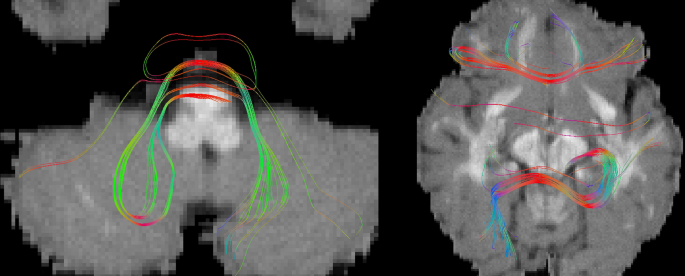

Erroneous bundle segmentation examples. (a) ILF (red) and OR (green) with (b) an example of sub-optimal bundle segmentation in submission 1.3 (using Recobundles). (c) FPT (pink), CST (orange), and POPT (blue), with (d) streamlines recovered for these bundles from all 2015 submissions. The GT bundle mask borders are shown in a darker contour. We can see that classification was sometimes arbitrary to one or the other bundle, particularly in the center.

Curation of the GT tractogram

The GT bundles were modified to enable the creation of the ROIs. Analysis of the GT tractogram revealed short/long, looping, and broken streamlines. Streamlines from the GT bundles were filtered to keep only those with length in the range 20–200 mm (generally streamlines presenting looping shapes) or recovered as loops using scilpy were discarded (see https://scilpy.readthedocs.io/). Other streamlines were discarded based on visual analysis of the bundles. Rejection was kept as small as possible to ensure good compatibility between the tractogram and the associated simulated DWI. CST, POPT, and FPT were too similar and difficult to segment adequately (Fig. 2) and were gathered into a new bundle called Brainstem Projection System (BPS). The ILF and OR were also too similar, preventing a good segmentation (Fig. 2), either with Recobundles or with ROIs. In this case, we chose to filter out some streamlines to better separate the two bundles. To assess the intensity of these changes, we scored this curated GT with the original scoring system.